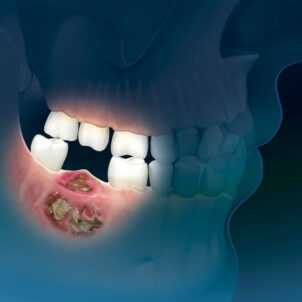

Остеогенная саркома альвеолярного отростка верхней челюсти

Остеогенная саркома нижней челюсти

Плеоморфная саркома мягких тканей шеи справа